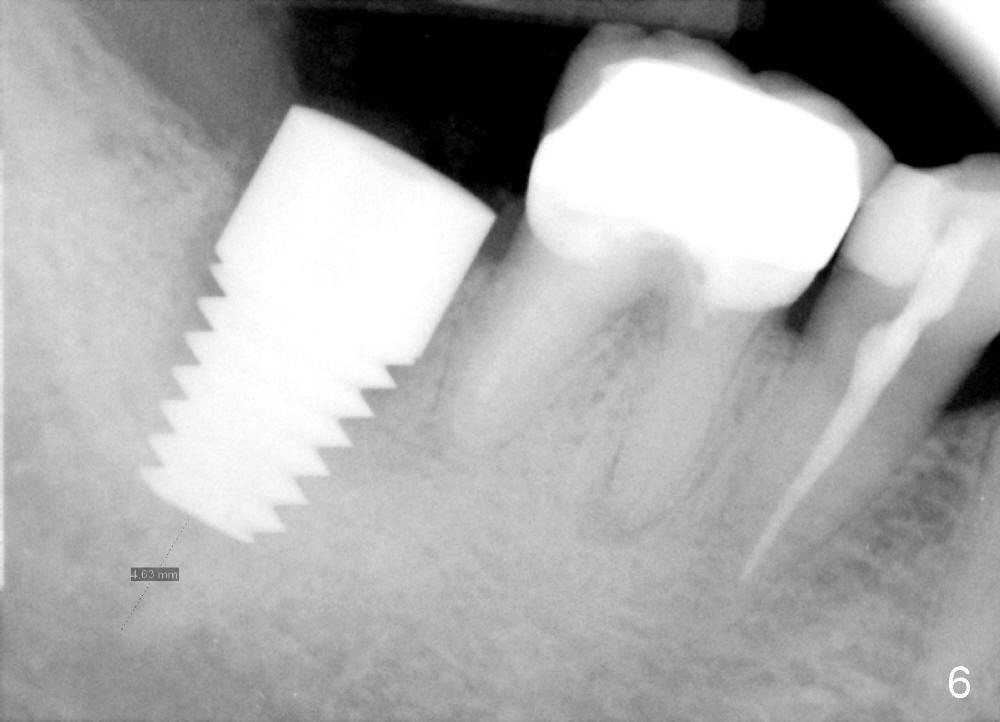

A 51-year-old man has experienced pain and swelling in the lower right 2nd molar for 7 months (Fig.1, P: post in the mesial root; <: gutta percha inserted into a buccal fistula). Fig.2 is taken immediately before extraction (<: purulent discharge from the mesiobuccal fistula) and immediate implant (Fig.3 implant design: 7x14 mm). A vertical root fracture is noted in the mesial root (Fig.4: lingual view). The septum is in fact absent, as compared to Fig.1. The mesiobuccal plate is low; the osteotomy starts lingual to the center of the socket. Fig.5 shows a 4.5x17 mm tap in place: approximately 3.5 mm in the new bone (~2.5 mm from the inferior alveolar canal). When a 7x17 mm tap (14 mm from the gingival margin) is placed in the socket, it looks relatively small. Fig.6 shows a 8x14 mm implant in place with a small gap distally. Mineralized cancellous allograft and Osteogen mixture is placed mainly buccally, followed by a thin strip of collagen dressing and sutures (Fig.7); an abutment (A) is placed to keep perio dressing in place. The perio dressing does not stay long. The buccal portion dislodges by itself 5 days postop. The lingual portion is removed in clinic. New dressing is going to be re-applied, because the buccal wound has not completely healed (Fig.8 <, albeit asymptomatic) with partial exposure of the bone graft (*). Why is the dressing lost so early? The abutment is not long enough; there is plenty of occlusal clearance (Fig.9 arrows). A longer abutment is used to increase mechanical retention for perio dressing (Fig.10). By the time the second perio dressing dislodges, the wound has healed (Fig.11, 13 days postop).

The patient returns for final restoration 5.5 months postop; it appears that the distal gap has disappeared (Fig.13 *). There is no bone loss 26 months post cementation (Fig.14). The lamina dura-like dense bone forms coronally 3 years 4 months post cementation (Fig.15 *). The 8 mm implant remains buried in the bone 5 years 4 months post cementation (Fig.16).